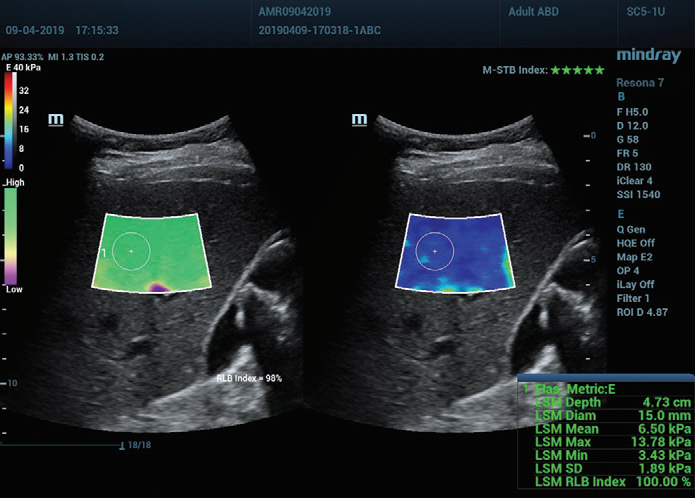

Afbeelding 1 (vervolgd): (e) Beelden verkregen met 2D SWE (STE; Mindray, Shenzhen, China). Er worden twee kwaliteitscriteria gegeven: de index voor bewegingsstabiliteit (M-STB), die wordt aangeduid met sterretjes (de hoogste stabiliteit wordt aangeduid met vijf groene sterretjes), en het betrouwbaarheidsraster (RLB: reliability), dat van paars naar groen gaat, waarbij groen de hoogste betrouwbaarheid aangeeft. De sterretjes zijn een indicator van beweging tijdens de verwerving. Bij minder dan vier sterretjes is er aanzienlijke beweging tijdens de verwerving en dat frame mag niet worden gebruikt voor de meting van de leverstijfheid. (f) Verkregen beelden.

Daarnaast biedt Mindray's Sound Touch Elastography (STE) krachtige kwaliteits- of betrouwbaarheidsfactoren, waaronder de M-STB-index (bewegingsstabiliteit), het betrouwbaarheidsraster (RLB), de betrouwbaarheidsindex (RLB), enz. voor metingen verkregen met 2D-Shear Wave-elastografie. Dit helpt operatoren de standaarden voor beeldverwerving te bevestigen.

De M-STB-index geeft de stabiliteit van de weefselbeweging aan die wordt veroorzaakt door de ademhaling van de patiënt of door compressie van de operator. Dit helpt bewegingsinterferentie te elimineren. Dit wordt aangegeven door sterretjes (de hoogste stabiliteit wordt aangeduid met vijf groene sterretjes). Een betrouwbaar beeld moet ≧4 groene sterretjes hebben.

Het RLB-raster geeft de betrouwbaarheid van STE-beelden aan en gaat van paars naar groen, waarbij groen de hoogste betrouwbaarheid aangeeft. Wanneer de RLB-index ≧90% is, is het beeld betrouwbaar.